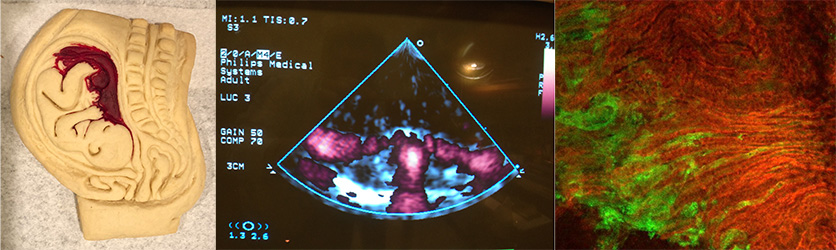

The Morgan Lab studies the underlying pathology that causes the great obstetric syndromes of fetal growth restriction, preeclampsia, and spontaneous preterm labor.  We have developed a mouse model that mimics the most common pathophysiology observed in women at the uteroplacental interface, which we employ to study molecular mechanisms, develop maternal blood-based diagnostic testing, and treatments to prevent these common and serious complications.  Results are then translated into non-human primate and human studies.  Our current focus is investigating the content and function of cell- and size-specific extracellular vesicles (virus sized plasma-membrane bound nanoparticles released by cells into the circulation) to better understand cell signaling and diagnostic potential.  A long-term aim of our group is to better understand the role of sex-specific fetal programming in the progeny's risk for disease (eg, cancer) and whether there are transgenerational risks that may be ameliorated.